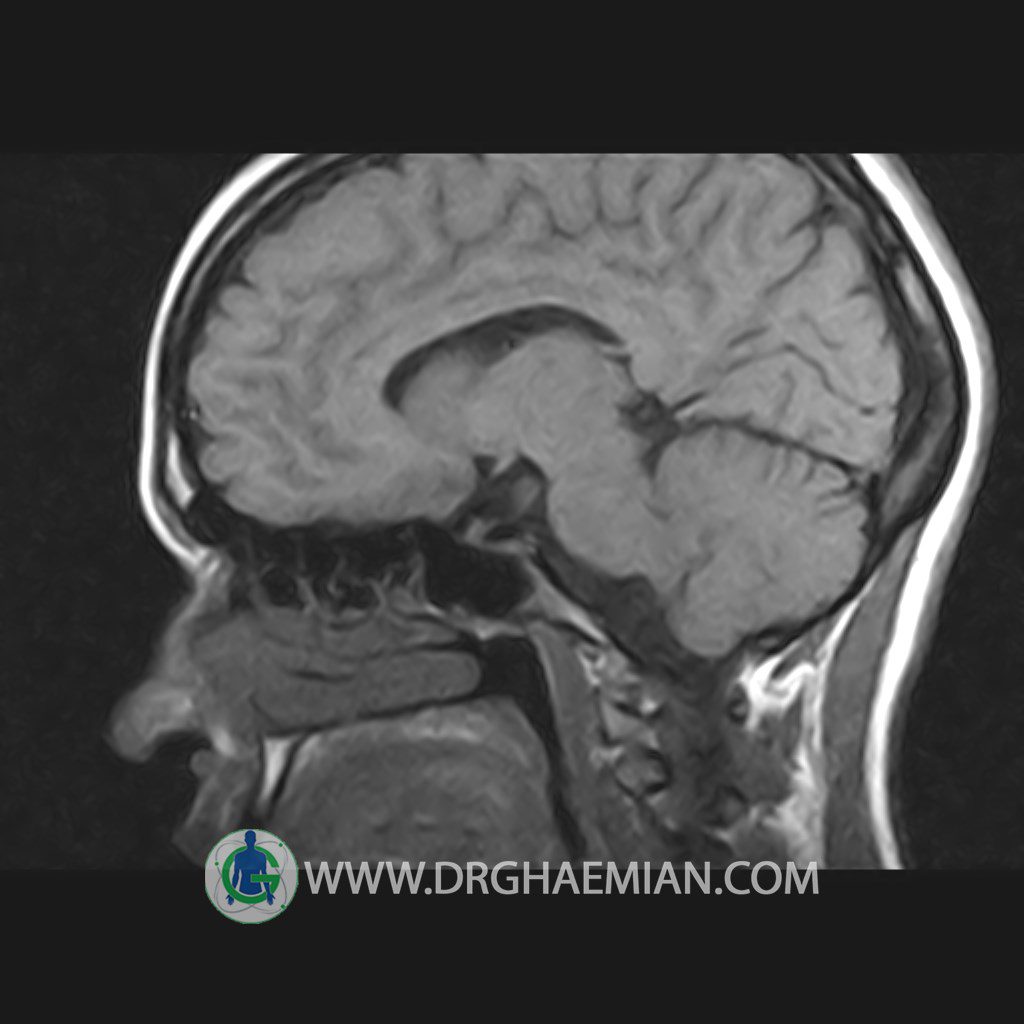

پزشکان اغلب از تصویربرداری ام آر آی برای تشخیص و درمان عارضه های پزشکی که فقط با استفاده از اشعه ایکس یا میدان مغناطیسی و امواج رادیویی قابل مشاهده است، استفاده می کنند. دستگاه ام آر آی تصاویر دقیق از ساختار های داخلی بدن ایجاد می کند. در این کیس هیپرپلازی هیپوفیز و آدنوم مشاهده می شود.

HYPOPHYSIS MRI

(with and without contrast)

Technique: Axial , coronal T1 , Axial , coronal , sagittal T2 , Axial, coronal T1 post Gd & 64 dynamic thin coronal slices.

REPORT :

The sella shows normal size , position and configuration .

The borders of its floor and walls are smooth and sharply defined .

The infundibulum is centered and of normal size .

The optic chiasm and suprasellar spaces appear normal .

The cavernous sinus and imaged portions of the internal carotid artery and carotid siphon are unremarkable .

Evaluable portions of the neurocranium show no abnormalities .

The sphenoid sinus is clear and pneumatized .

– Mild convexity at superior border of pituitary gland with post contrast homogeneous enhancement suggestive for pituitary hyperplasia & iso signal adenoma

is seen